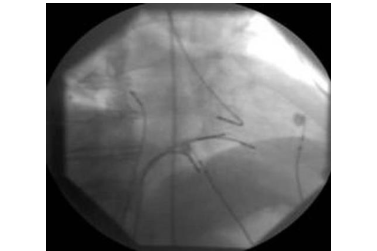

ECG recordings from the body surface are often not sufficient for an accurate diagnosis of arrhythmia. ECGs" directly from the heart are then required. For this purpose, thin electrodes are placed in the patient's heart via the vein in the groin under sedoanalgesia and after local anaesthesia in order to record the electrical activation there directly (Fig. 1)